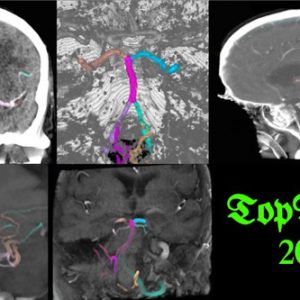

[MICCAI TopBrain2025 Grand Challenge] 오관석 수상

Congratulations!!! Kwanseok achieved excellent results in the TopBrain2025 Grand Challenge held at MICCAI. His team ranked in multi-class segmentation tasks as follows: Segmentation (CT Angio): 1st placeSegmentation (MR Angio): 2nd place He will be awarded official certificates and prizes in recognition of their outstanding performance.